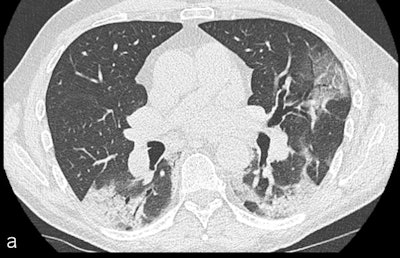

Of the 72 patients who underwent CTPA, 80% also had a positive RT-PCR test for SARS-CoV-2. CTPA identified embolism on 13 scans (18%). Of these, two had main, four had lobar, and seven had segmental acute pulmonary embolism. The most commonly affected lung segments were right lower lobe (61%) and left lower lobe (54%).

Ground-glass opacity | 85% | 97% | 0.147 |

Consolidation | 69% | 68% | 1 |

Crazy paving | 38% | 37% | 1 |

Linear reticulation | 69% | 78% | 0.490 |